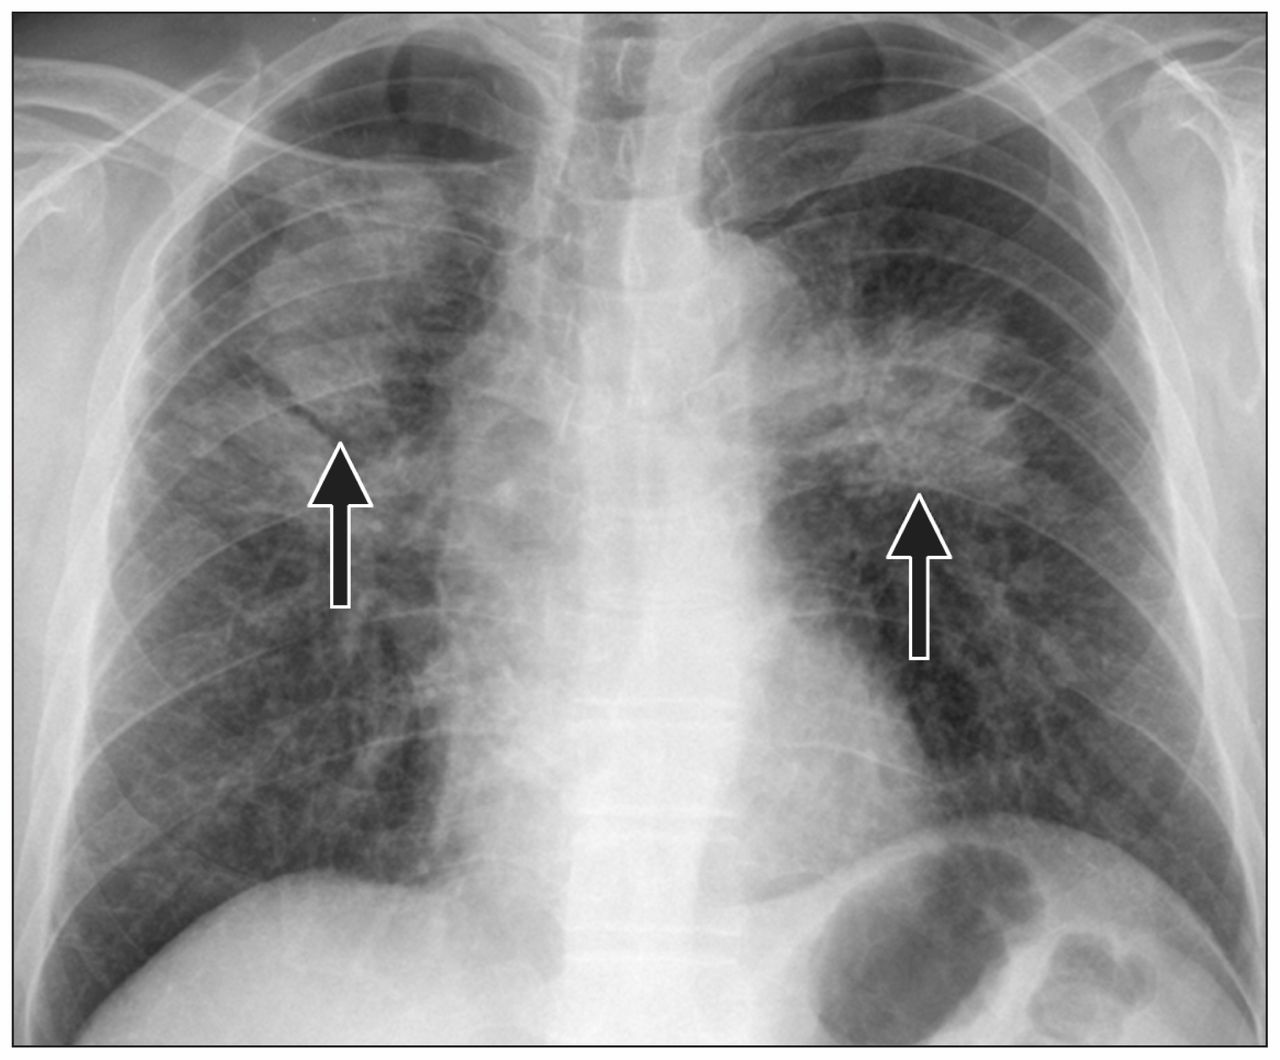

Фотографии, демонстрирующие обнаруженное усиление легочного рисунка

Раздел: Фотодневник открытий